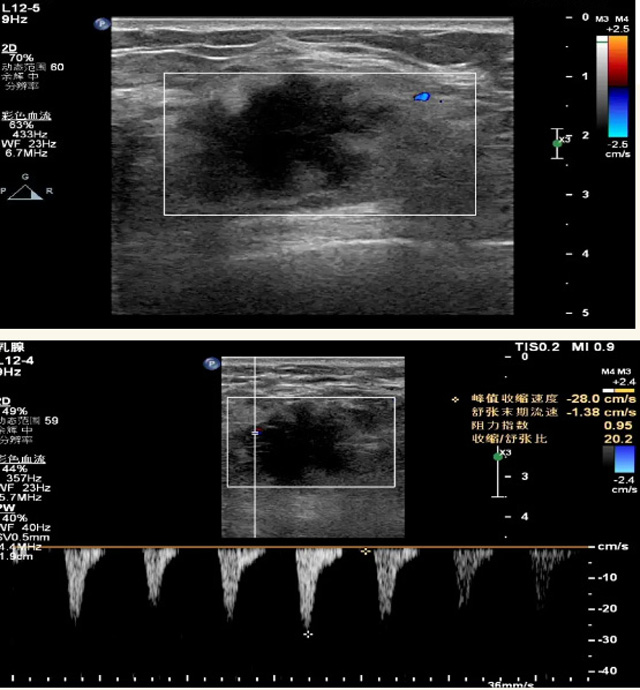

乳腺B超檢查無輻射,對囊性病變敏感,可以實時觀察病灶。超聲引導活檢跟手術前的定位。就是它對于微小的鈣化查出率比鉬靶稍微差點。磁共振MRI檢查也是是沒有輻射的,對備孕跟已經懷孕的人士比較友好。不用擔心這個輻射影響胎兒問題。對乳腺病灶敏感性較高,致密乳腺病灶、乳腺癌的復發,準確鑒別囊性及實性病變。可以幫助臨床醫生判斷惡性、良性病變。但是MRI磁共振對微小鈣化不明顯,微鈣化還是鉬靶靠譜點。檢查時間比較長,有偽影的影響。費用相對B超,鉬靶高很多。